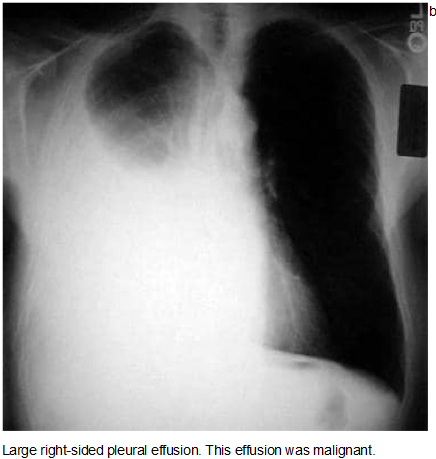

Chest Radiography

Effusions of more than

175 mL are usually apparent as blunting of the

costophrenic angle on upright posteroanterior

chest radiographs. On supine chest radiographs,

which are commonly used in the intensive care

setting, moderate to large pleural effusions may

appear as a homogeneous increase in density

spread over the lower lung fields. Apparent

elevation of the hemidiaphragm, lateral

displacement of the dome of the diaphragm, or

increased distance between the apparent left

hemidiaphragm and the gastric air bubble

suggests subpulmonic effusions.